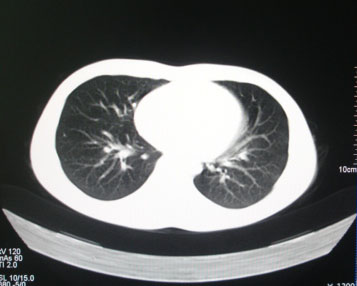

标题: CT26938:单发肺窗

病人17岁。咳嗽伴血丝痰2年?外院x片示左上肺椭圆形影,疑胸腺瘤

左肺尖见占位,建议上传纵隔窗及向上扫描。

左上纵隔占位性病变?